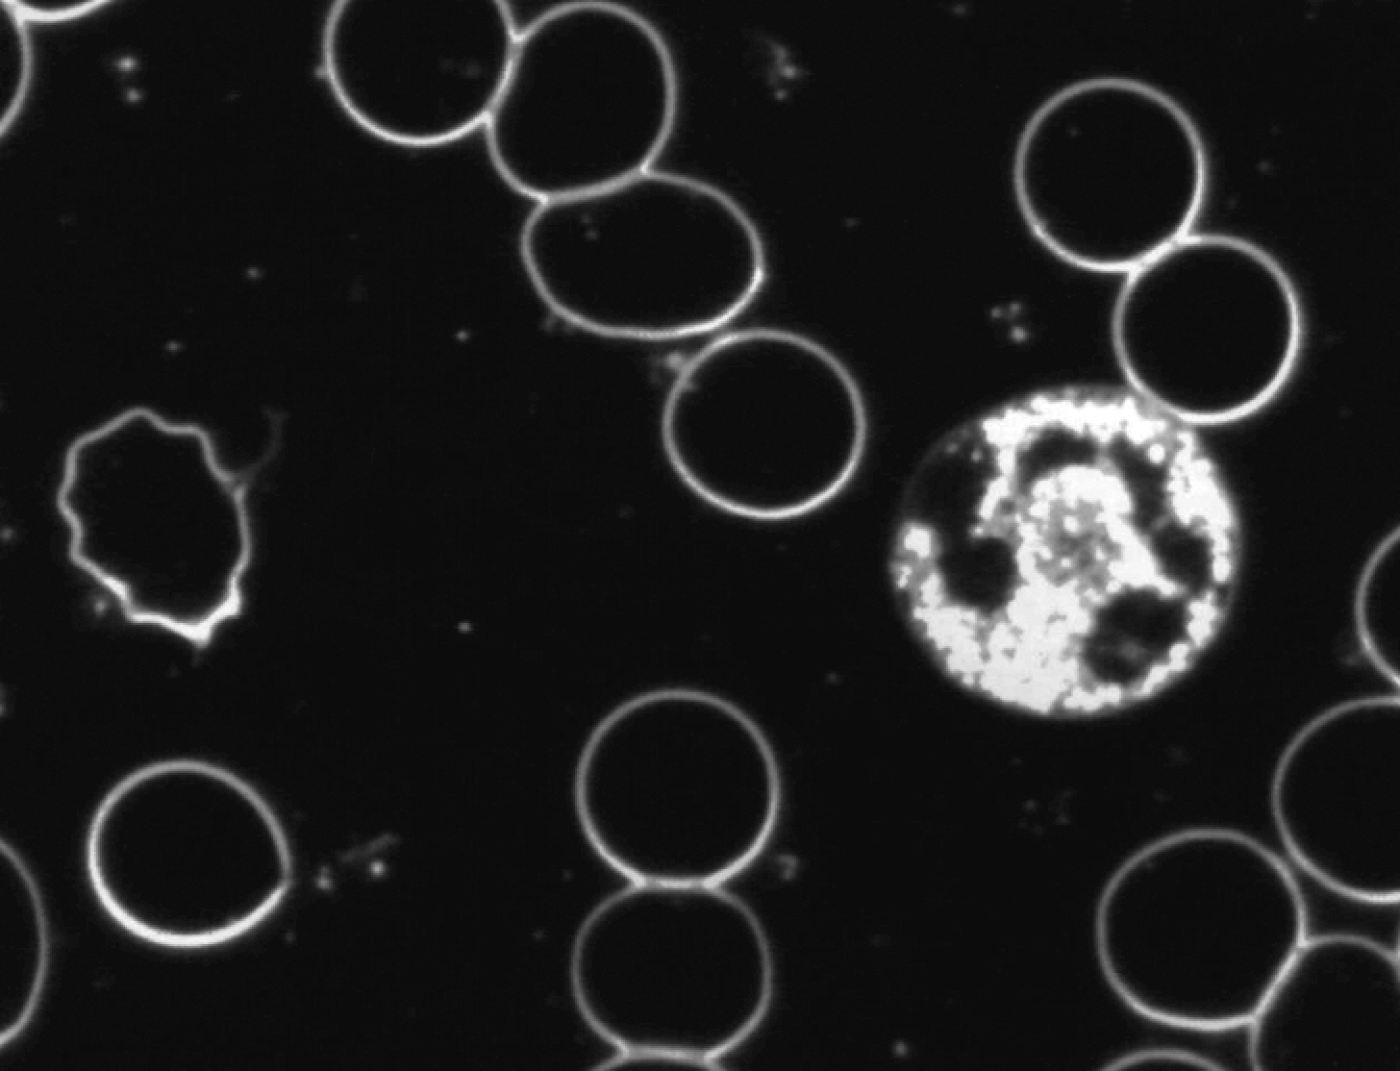

Zie ook onderstaande foto’s met een karakteristiek beeld van vóór en na de neutralisatie met Benzoliet.

Levend bloedbeeld

na neutralisatie met Benzoliet

De veranderingen die werden geconstateerd na neutralisatie van de toegepaste verstorende subtiele energieën door Benzoliet in met name de witte cellen waren:

- toegenomen mobiliteit

- toegenomen en homogeen over de cel verspreide cytoplasmatische activiteit

- verlaten van de bolvorm

- het vormen van pseudopodieën

Hieruit volgt de conclusie dat Benzoliet in staat is de in de proef toegepaste verstorende subtiele energieën te neutraliseren en dat door neutralisatie het afweersysteem beter kan functioneren.